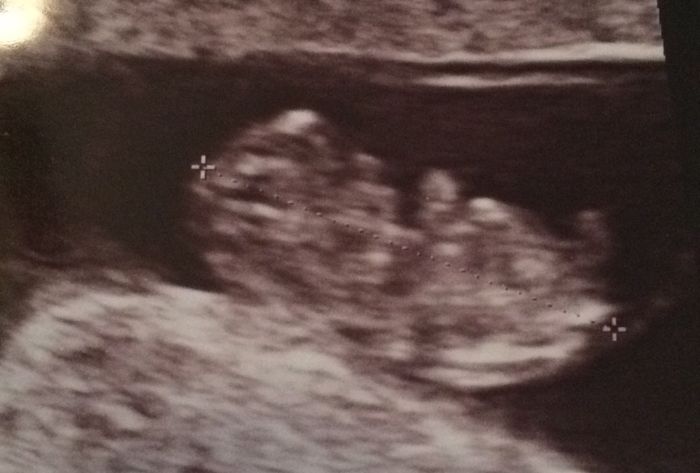

Prima eco